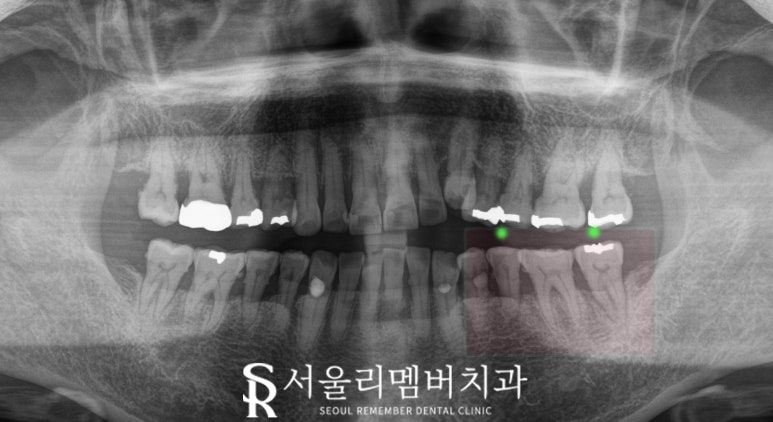

하악 좌측 구치부에서

식사를 할 때마다 불편감이 나타나고 있으며

임상 검사 시,

두 번째 작은 어금니(35번)와

두 번째 큰 어금니(37번)에

동요도(MOB, Mobility)가 관찰되었습니다.

그러다 보니 음식을 저작할 때마다

통증이 동반되었을 것이며

잇몸도 부어있습니다.

특히 37번에서는

치아 균열(Crack)이 발견되었는데요,

의료용 솜(cotton roll)과

바이트 스틱(bite slooth)으로

살짝 깨물어 보았을 때

찌릿한 통증이 나타나는 것을 보아

전형적인 crack syndrome을

의심해 볼 수 있습니다.